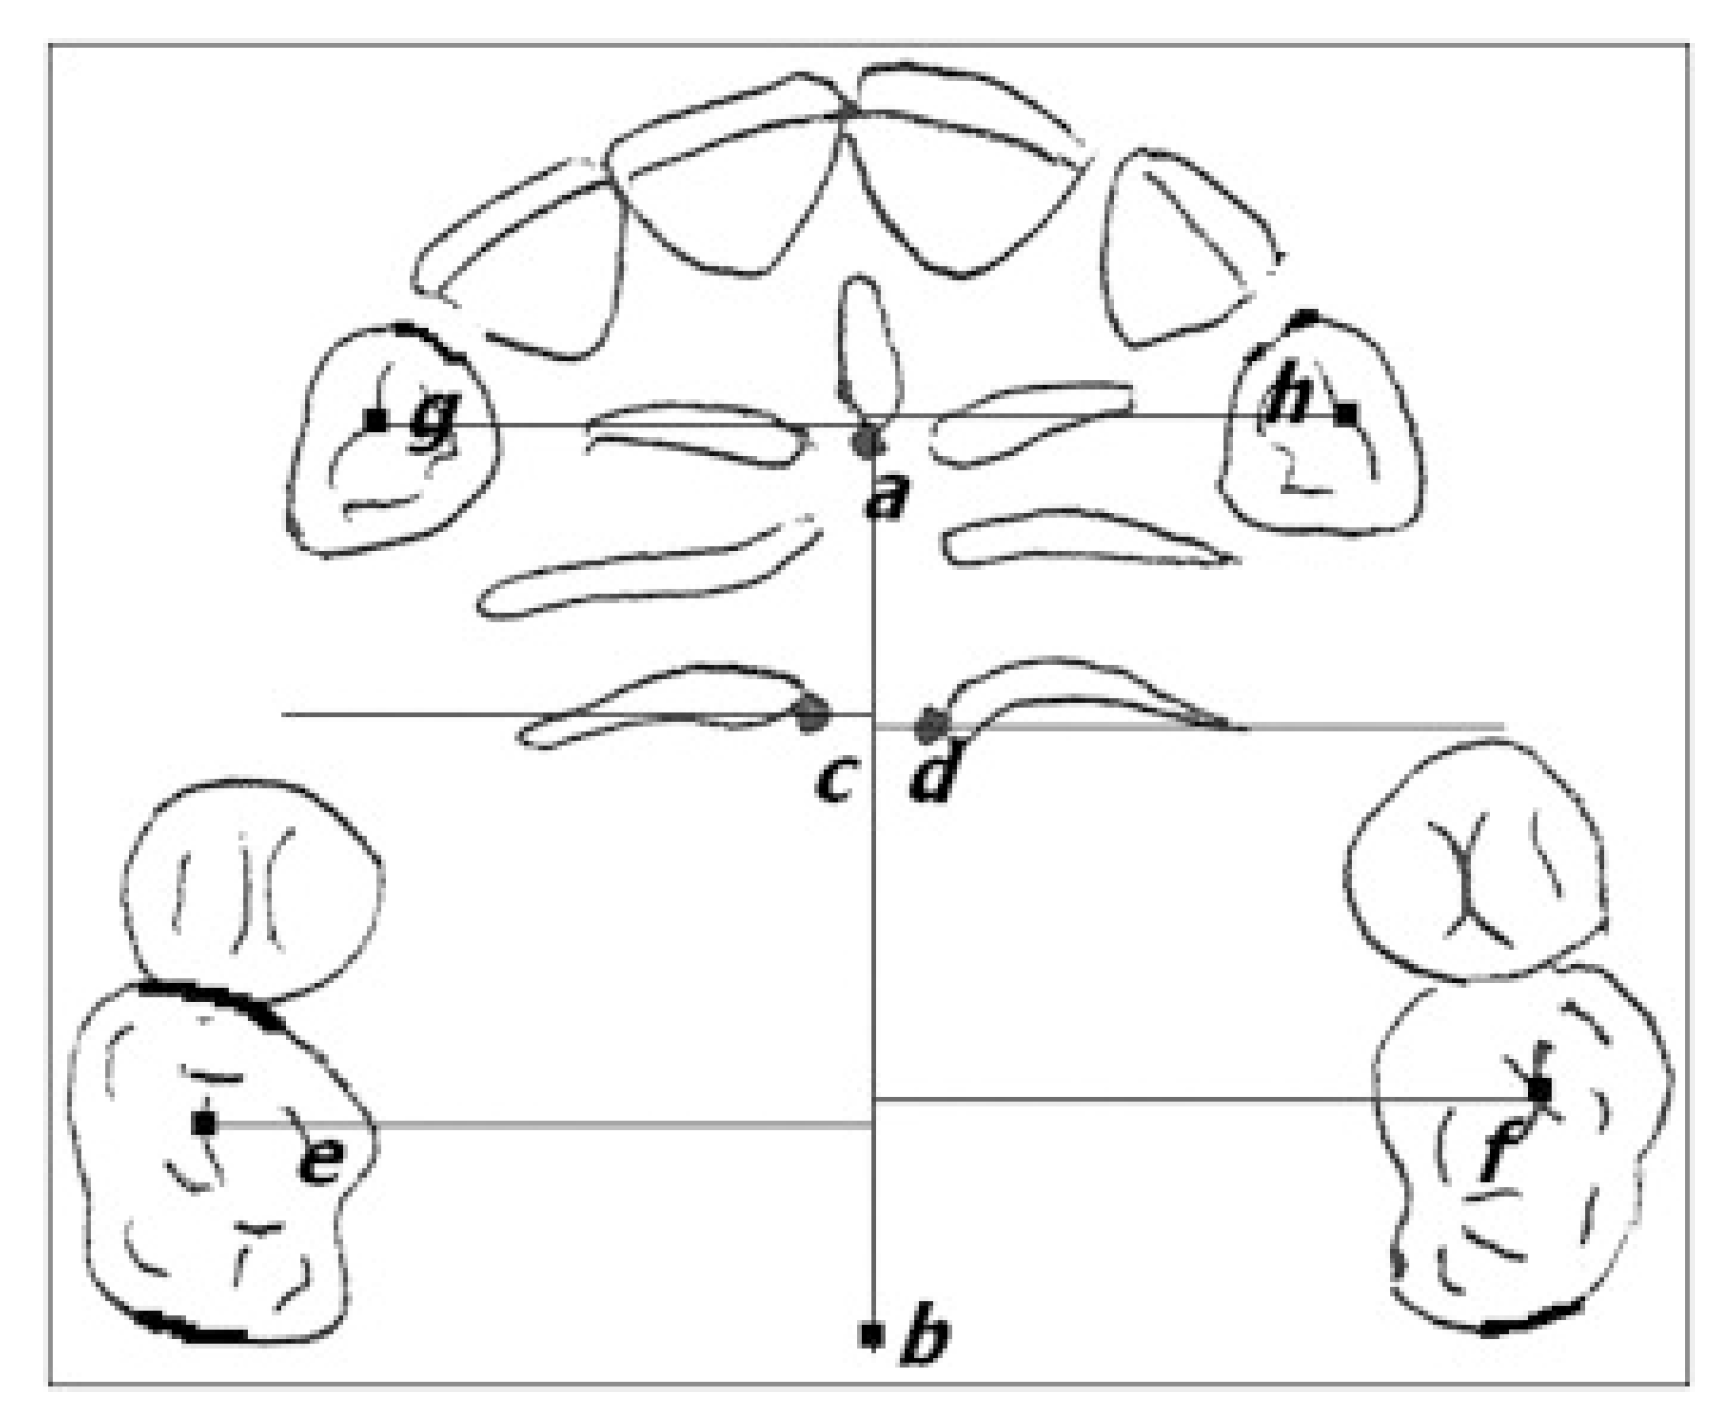

- -

- cusp of the canine;

- -

- mesio-vestibular cusp of the first molar;

- -

- median palatine raphe;

- -

- most medial point of the third palatine wrinkle (points C and D);

- -

- central fossa of the first molars (points E and F);